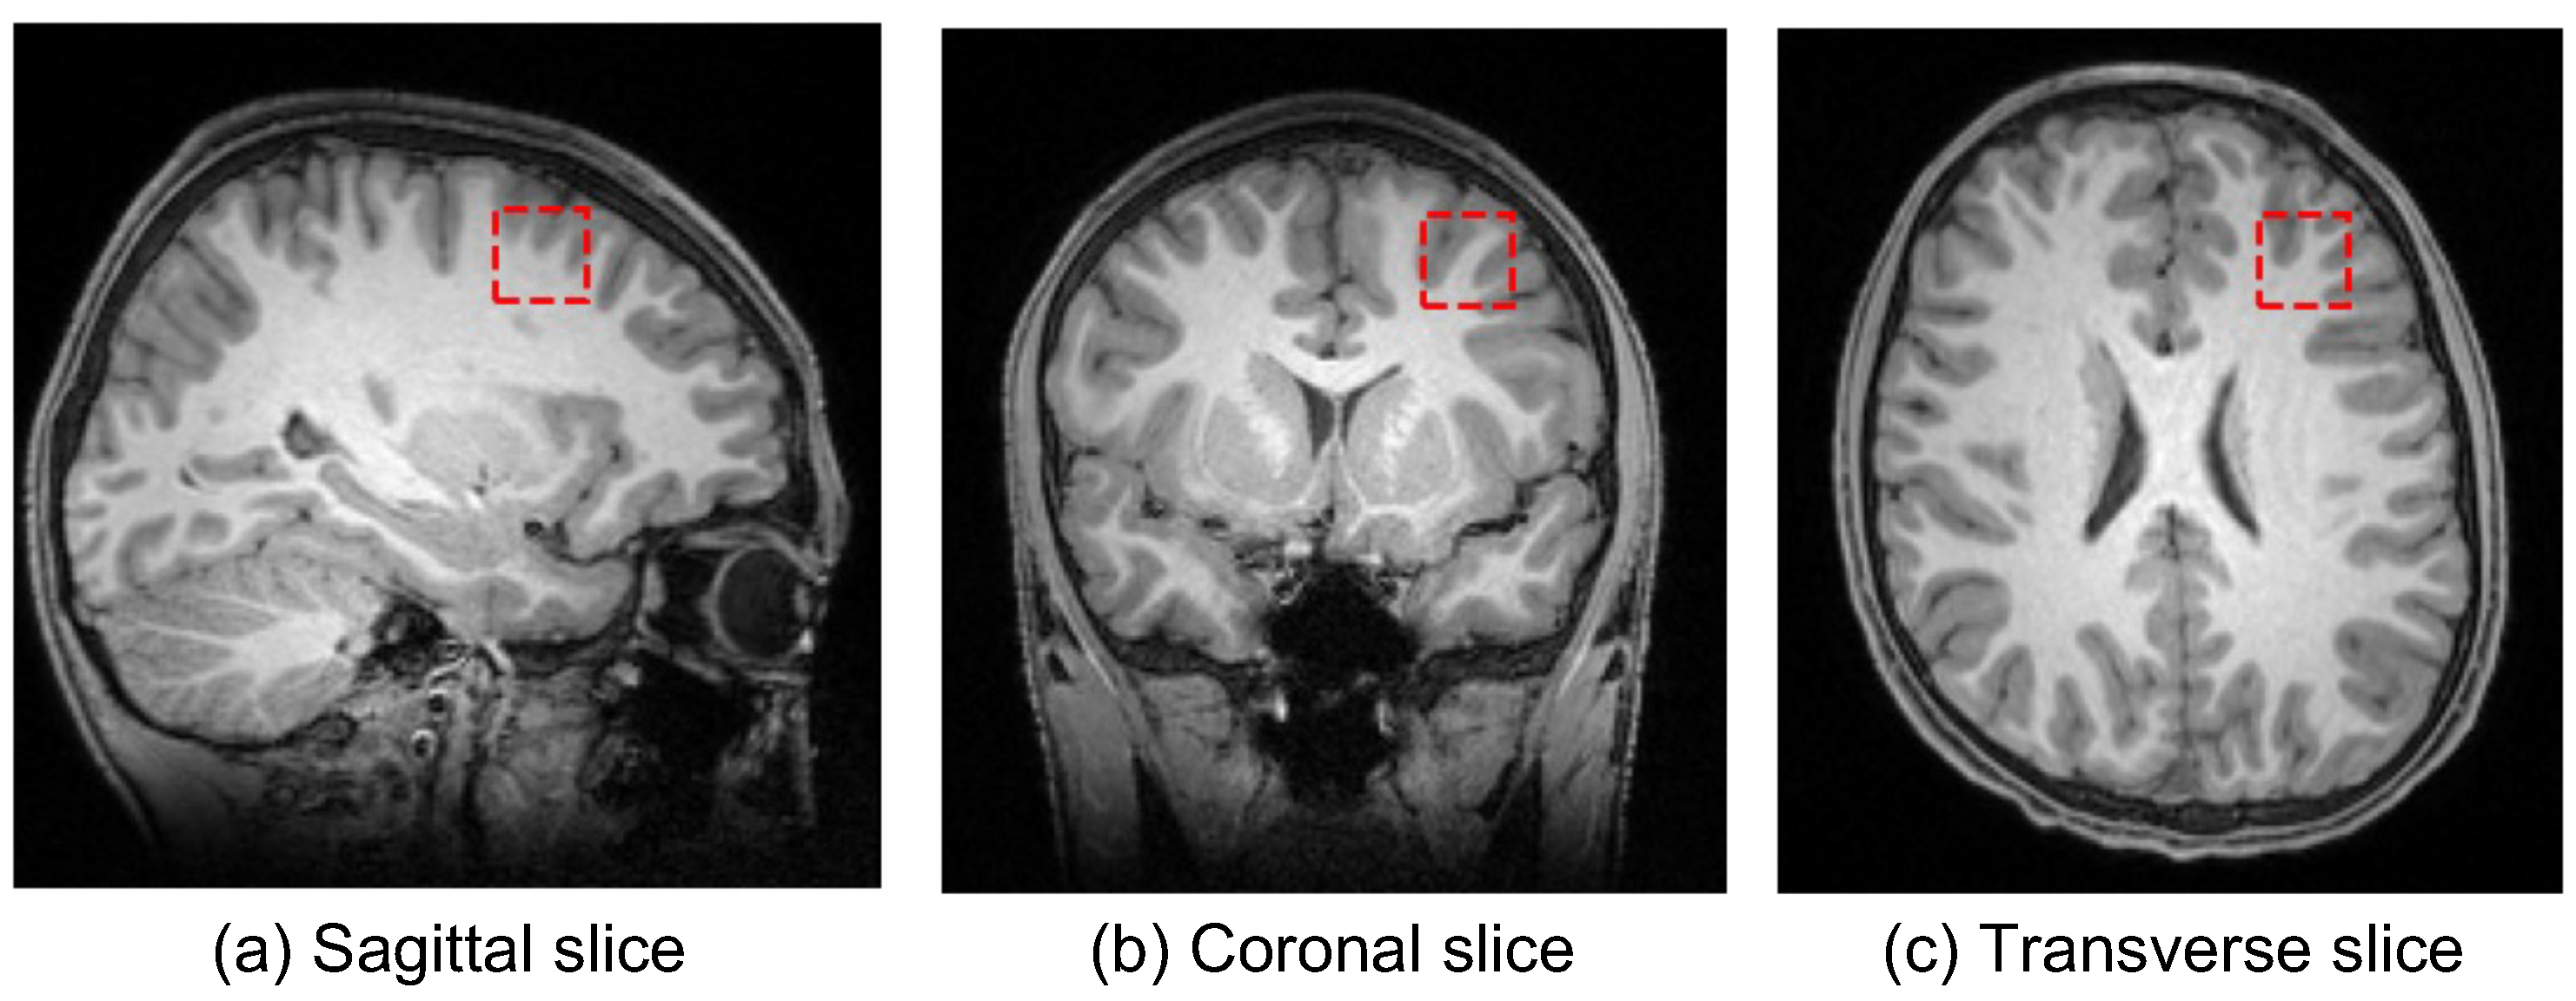

2.1. MRI Data and Preprocessing